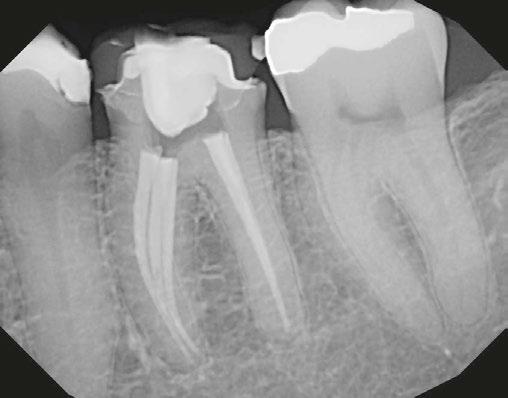

A 48-year-old female patient presented to the graduate endodontic clinic with a referral to evaluate and treat tooth No. 11 through the existing crown. The patient’s chief complaint was, “I was told a year ago I had an infection, but it hasn’t bothered me. They told me I needed a root canal to get rid of the infection.” The patient had no significant health history or any known drug allergies. Dental history for tooth No.11 included multiple restorations followed by a final core and crown in 2019. The adjacent tooth, No. 12, was replaced with an implant in 2018 and restored in 2019, 6 months following final crown of tooth No. 11. Upon examination of records, a periapical radiolucency on tooth No. 11 was visible on the day of crown fabrication and delivery (Figure 1). There was no note of this lesion in the patient’s record. An updated radiograph was taken during a periodic oral exam in September of 2023 showing clear delineation of the periapical radiolucency on tooth No.11 (Figure 2).

Upon presentation to the endodontic clinic, the patient was asymptomatic. Extraoral exam revealed no signs of acute infection and no lymphadenopathy. Intraoral exam showed no signs of acute infection and no sinus tracts. The crown on tooth No. 11 had adequate margins, contacts, and no recurrent decay was detected. Endodontic testing revealed negative responses to cold, percussion, and palpation. Probing depths of tooth No.11 and adjacent implant No. 12 were equal to or less than 3 mm, and no mobility was recorded. Radiographic examination revealed a periapical radiolucency present on the distal aspect of the root apex extending toward implant No. 12. Diffuse calcification in the coronal portion of the canal was observed, and no caries was noted (Figure 3).

Figure 1 (left): Periapical radiograph taken at the time of tooth No. 11 crown delivery in 2018 with a periapical radiolucency extending distally toward implant No. 12. Figure 2 (right): Updated periapical radiograph taken in 2023 during a periodic oral exam showing clear delineation of a periapical radiolucency associated with tooth No. 11

Figure 3: Periapical radiographs taken during endodontic consultation in 2023. Periapical radiolucency originated from tooth No. 11 and extended toward implant No. 12. Calcification was appreciated in the coronal portion of the canal space on tooth No. 11